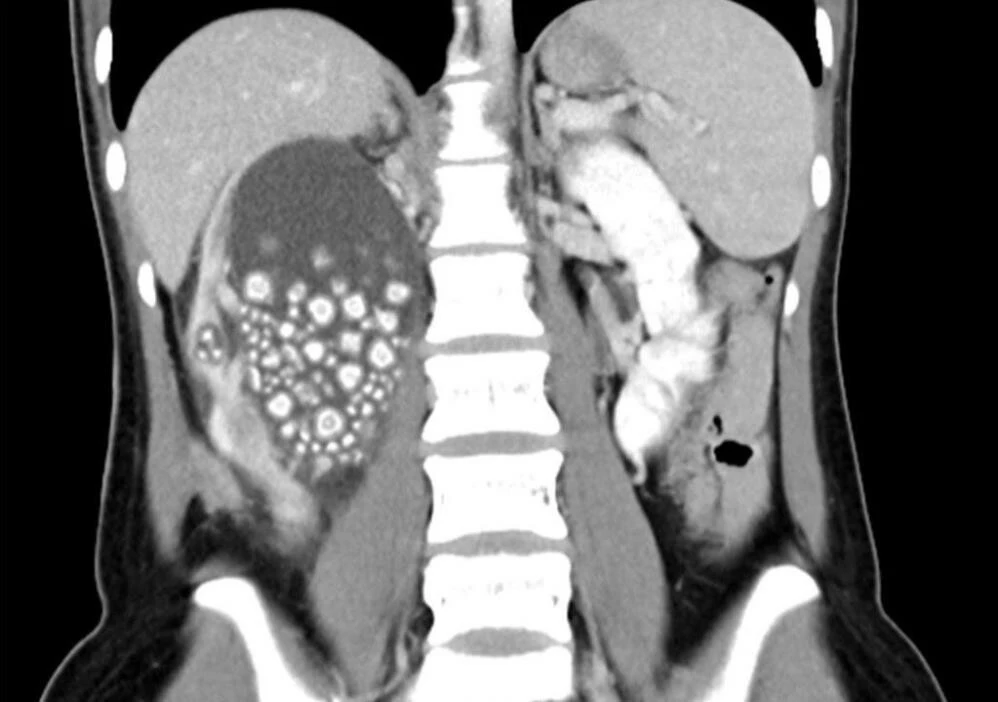

Tayvan'ın güneyinde bulunan Tainan şehrinde hayatını idame ettiren 20 yaşındaki Xiao Yu, sırt ağrısı şikayetiyle başvurduğu hastanede neye uğradığını şaşırdı. Hastanede yapılan tetkiklerin ardından Yu'ya doktorlar böbreklerinde çok sayıda taş olduğunu söylediler. Acil olarak ameliyata alınan genç kadının böbreklerinden 0.5-2 cm boyutlarında 300’den fazla böbrek taşı çıkarıldı.

Ameliyatın yapıldığı Chi Mei Hastanesi tarafından yapılan açıklamada, Yu’nun su içmeyi sevmediği ve sadece şekerli içecekler ile çay tükettiği belirtildi. Xiao Yu’nun beslenme alışkanlıklarının kötü olduğunu vurgulayan Chi Mei Hastanesi'ndeki doktorlar ise, Tayvanlılara daha sağlıklı gıdalar tüketmeleri ve bol bol su içmeleri konusunda uyarılarda bulundu.